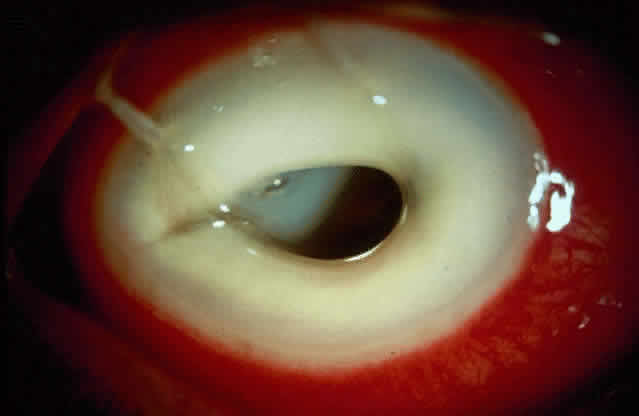

Active corneal infections in advanced stages are encountered more often by corneal surgeons in developing countries compared with their counterparts in developed countries (Fig. 8). The extent of corneal involvement associated with other intraocular damage often compromises the success of corneal transplantation. In a series from our institution, the success rate for graft clarity was poorer24 compared with other series.25 Ophthalmologists involved in corneal surgery should be familiar with this information and be prepared for the necessary intraoperative manipulations (Fig. 9).

Fig. 8. Corneal ulcer with extensive necrosis and perforation in the superior part.

Fig. 9. Large central perforation in a case of infectious keratitis.